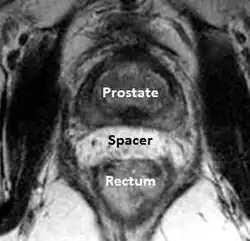

A new method to reduce rectal radiation injury in prostate cancer patients involves the use of an absorbable spacer placed between the prostate and rectum.

MRI showing hydrogel spacer pushing the rectum away from the prostate during radiotherapy.

Such spacers are commercially available in some regions and are undergoing clinical trials in others.[31] By temporarily altering the anatomy these products have the potential to allow for improved cancer targeting while minimizing risk to neighboring healthy tissues. Prostate rectum spacers should be compatible with all prostate cancer radiotherapy treatments including 3D conformal, IMRT and stereotactic radiation and brachytherapy.